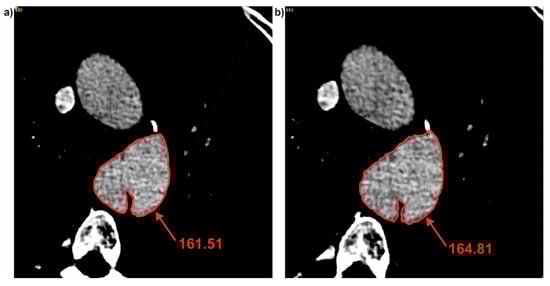

3.2. Brightness Value Analysis

| Patient | Average Brightness | ||

|---|---|---|---|

| Common | True | False | |

| Pat I | 184.73 ± 16.75 | 141.36 ± 20.26 | 178.01 ± 6.04 |

| Pat II | 331.11 ± 18.41 | 364.03 ± 14.10 | 320.10 ± 12.60 |

| Pat III | 291.13 ± 6.60 | 213.52 ± 39.70 | 313.91 ± 8.62 |